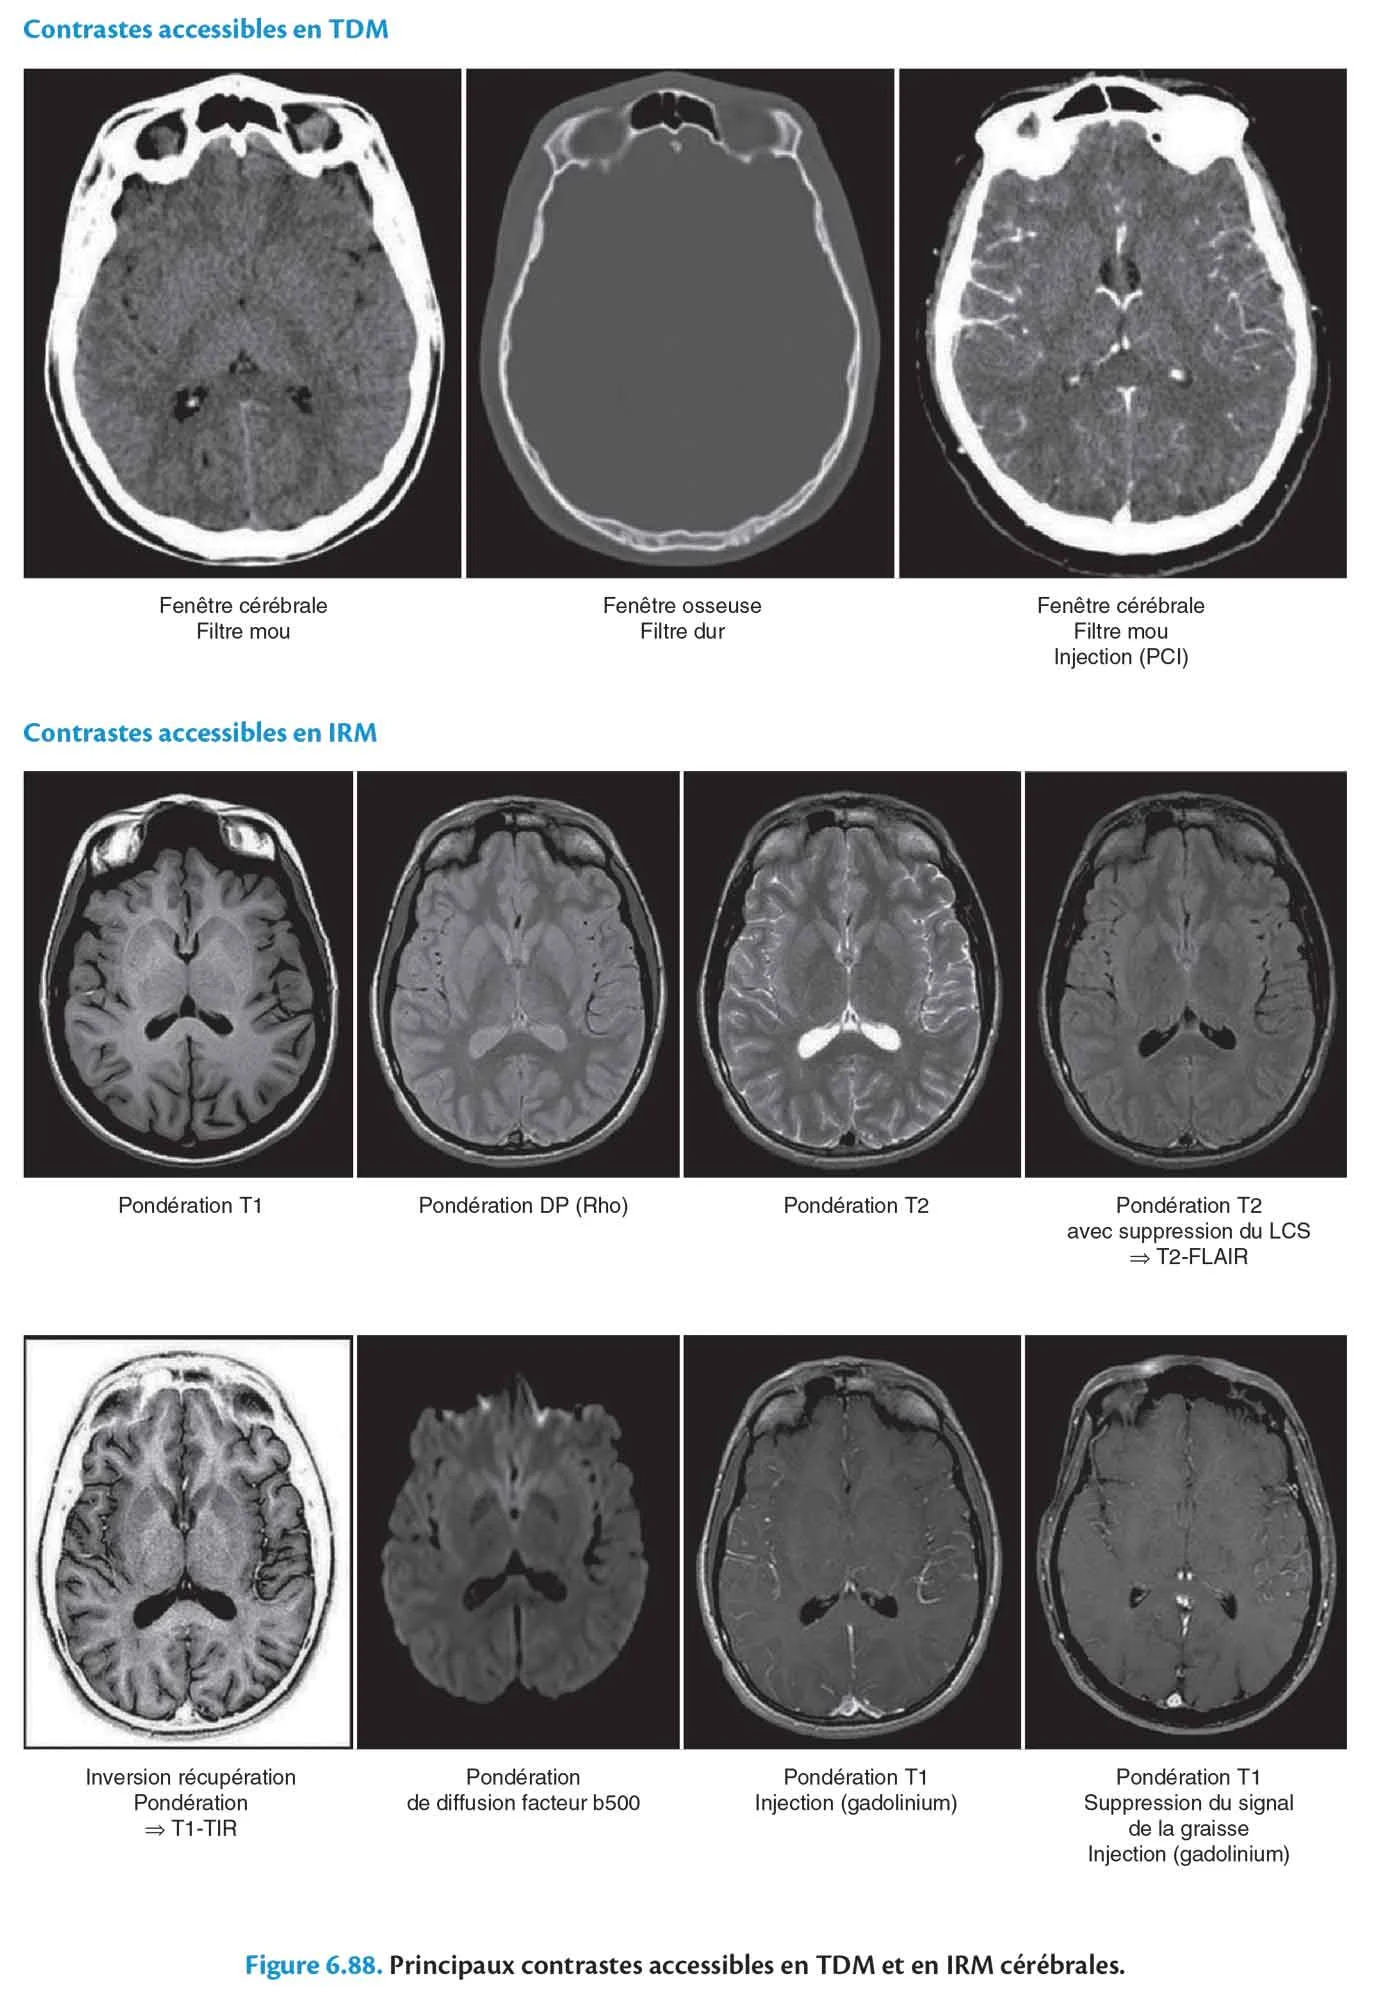

Contrastes accessibles en TDM

Fig 6.88